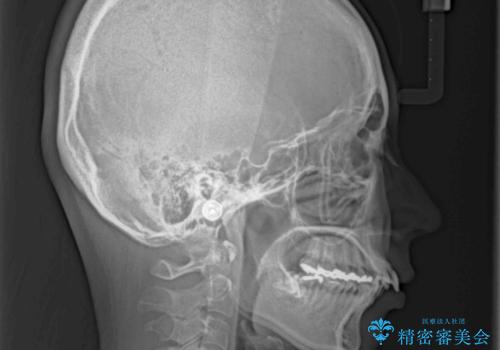

- 上下の出っ歯を気にして来院された患者様です。

口元を積極的に引っ込めるために、上下左右の第一小臼歯を4本抜歯することとしました。

元々ディープバイトのため、スペースを閉じている期間に上下前歯が接触してしまい、治療期間が想定よりも伸びてしまいました。